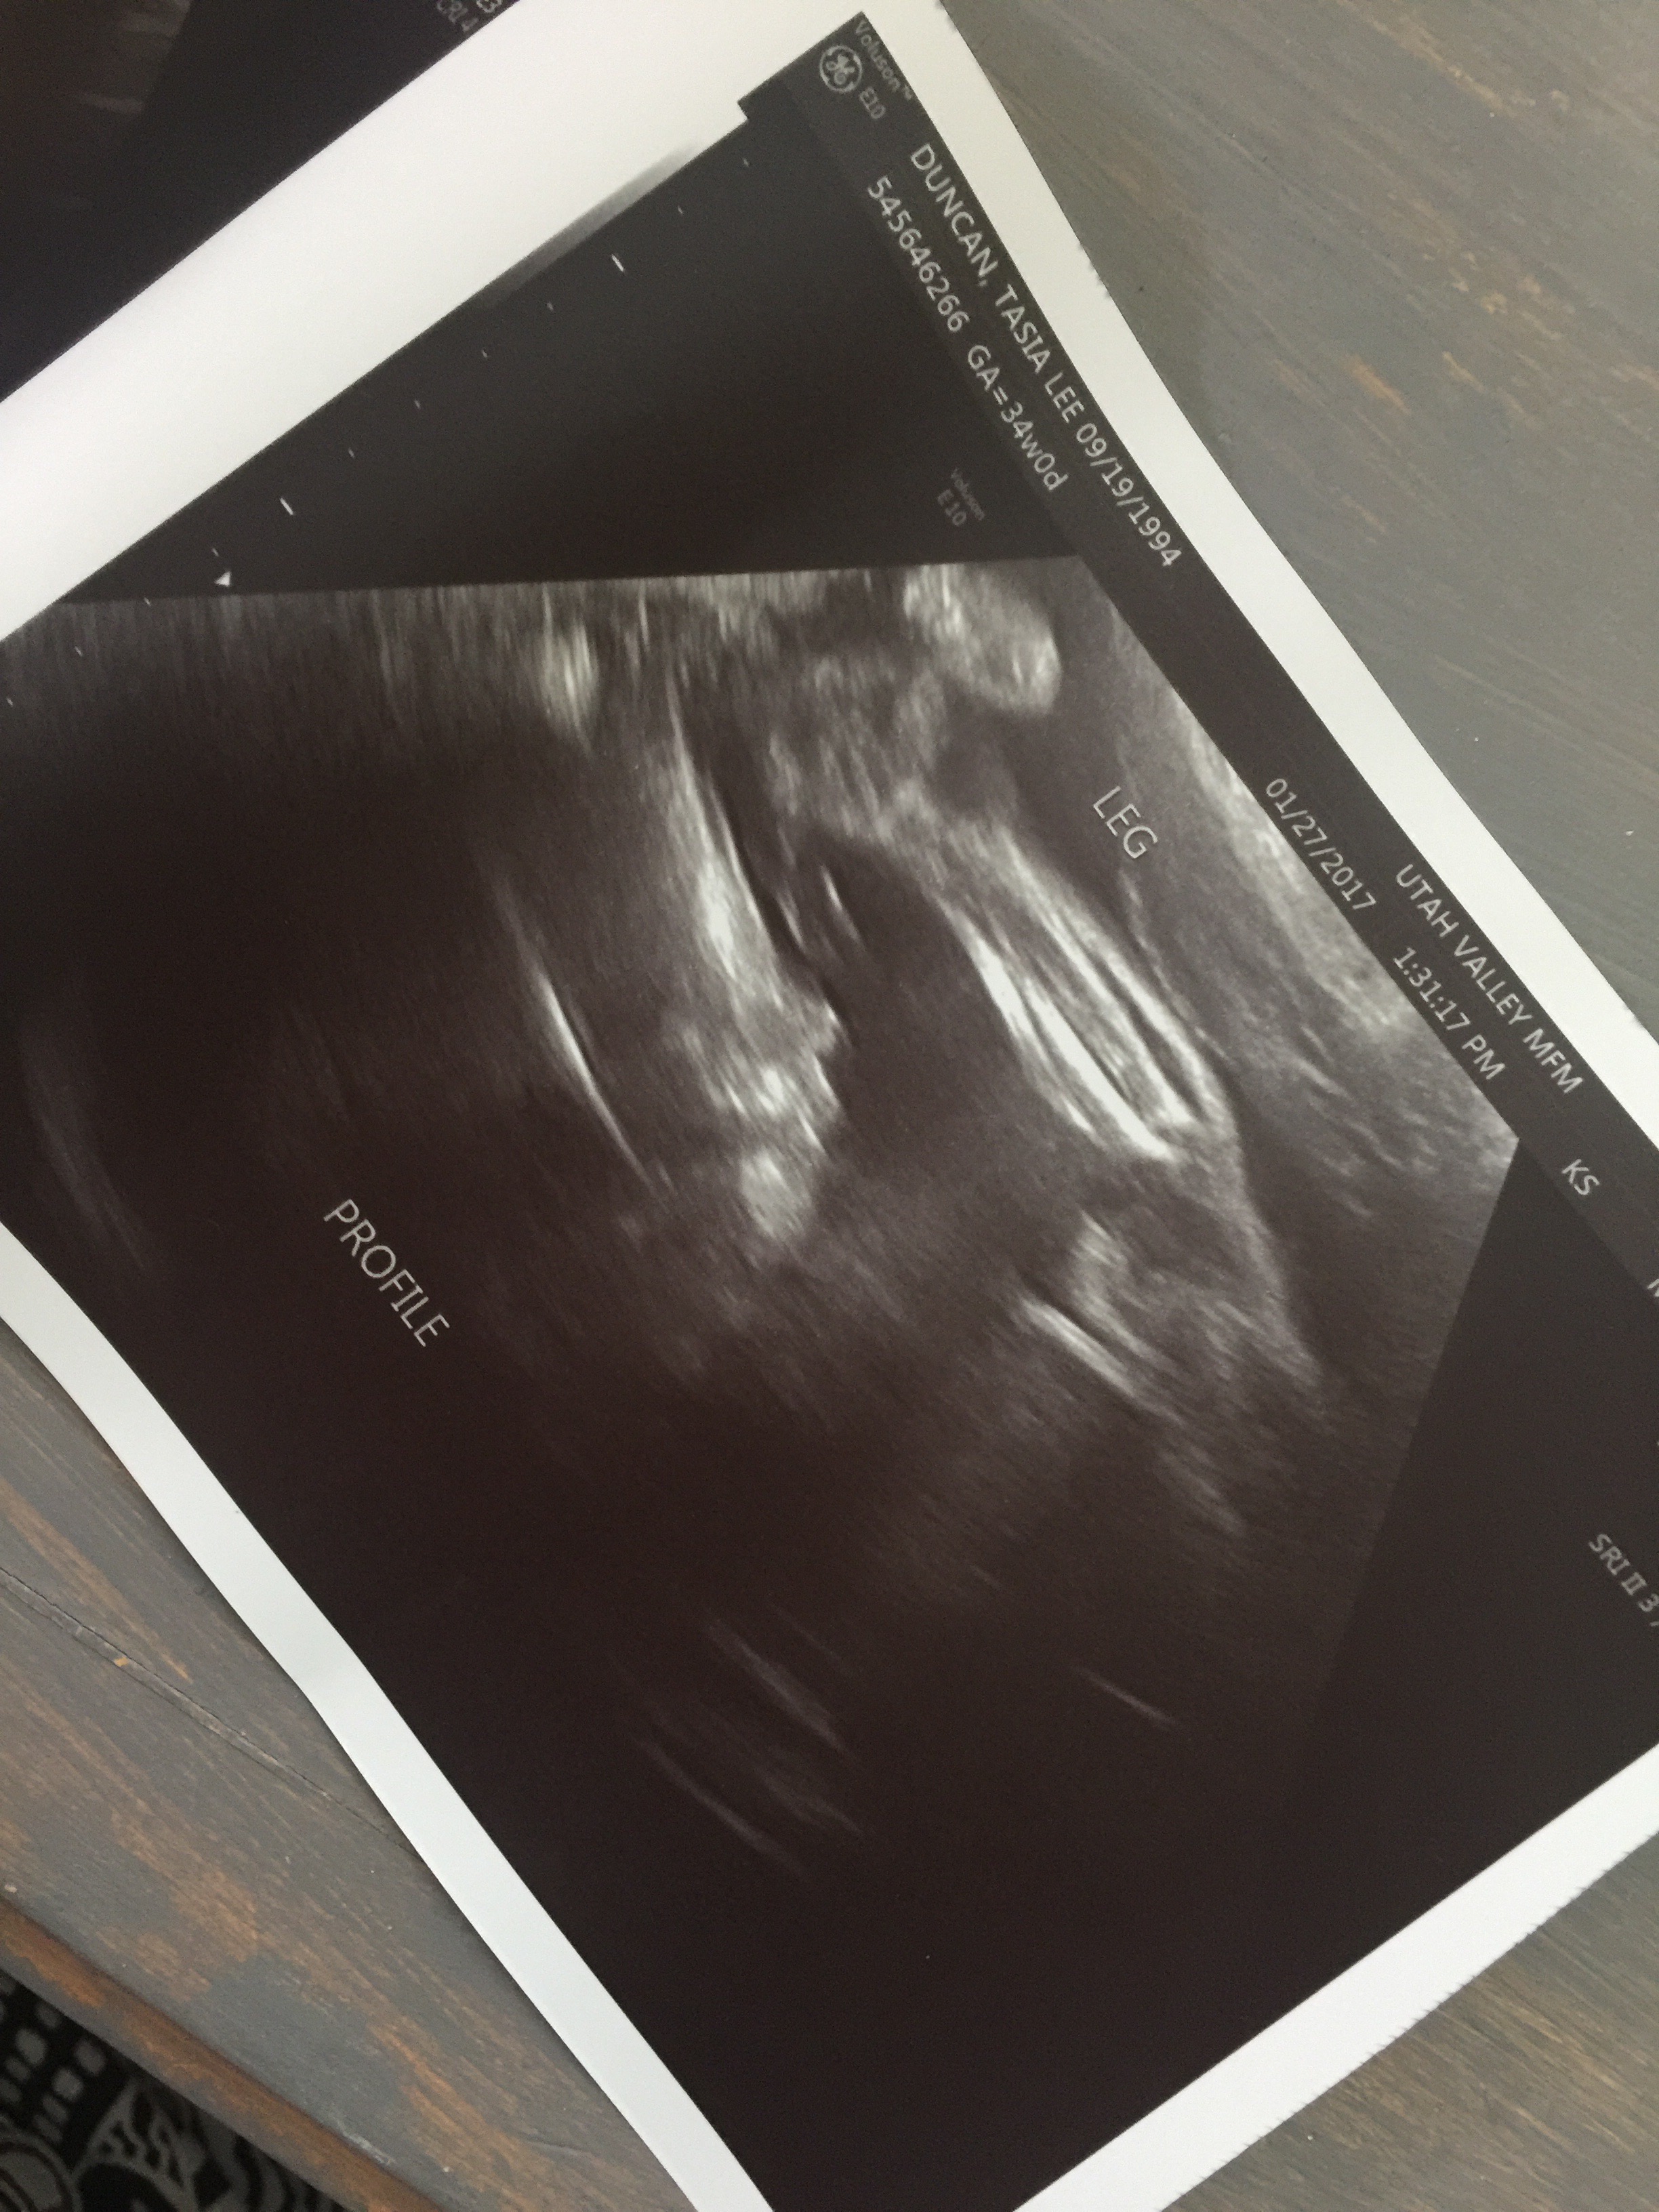

We did another ultrasound, this time on the whole baby. I love seeing her sweet face. I just can’t wait to kiss her face.

She was only measuring about 3 pounds 13 ounces. So she is definitely still little so I really need to keep her put for at least 3 more weeks. If I can make it to 38 weeks {in just 4 weeks} I will be so happy!